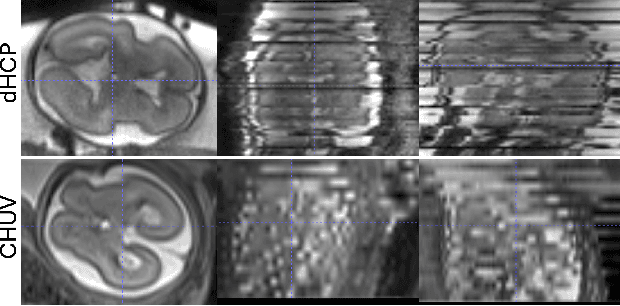

Abstract:High-resolution slice-to-volume reconstruction (SVR) from multiple motion-corrupted low-resolution 2D slices constitutes a critical step in image-based diagnostics of moving subjects, such as fetal brain Magnetic Resonance Imaging (MRI). Existing solutions struggle with image artifacts and severe subject motion or require slice pre-alignment to achieve satisfying reconstruction performance. We propose a novel SVR method to enable fast and accurate MRI reconstruction even in cases of severe image and motion corruption. Our approach performs motion correction, outlier handling, and super-resolution reconstruction with all operations being entirely based on implicit neural representations. The model can be initialized with task-specific priors through fully self-supervised meta-learning on either simulated or real-world data. In extensive experiments including over 480 reconstructions of simulated and clinical MRI brain data from different centers, we prove the utility of our method in cases of severe subject motion and image artifacts. Our results demonstrate improvements in reconstruction quality, especially in the presence of severe motion, compared to state-of-the-art methods, and up to 50% reduction in reconstruction time.